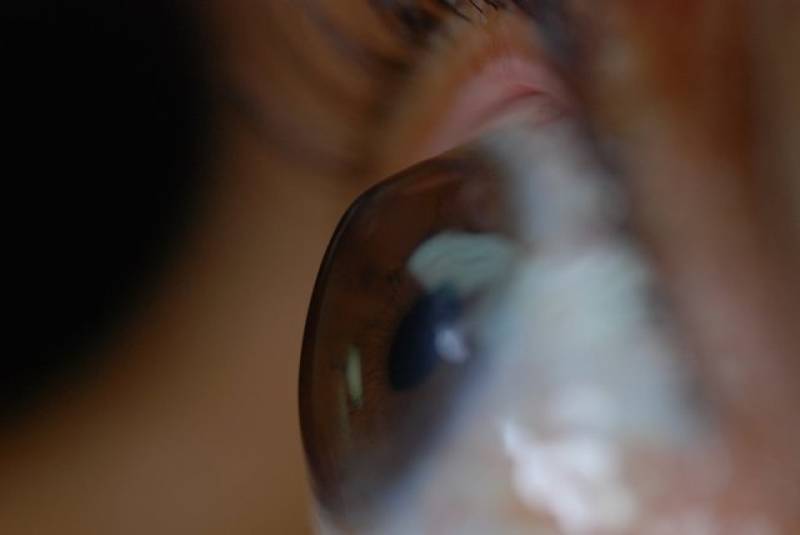

با تشخیص به‌موقع قوز قرنیه، نیاز به پیوند ندارید

با تشخیص به‌موقع، کنترل و درمان قوز قرنیه می‌توان از پیشروی و پیوند قرنیه پیشگیری کرد.